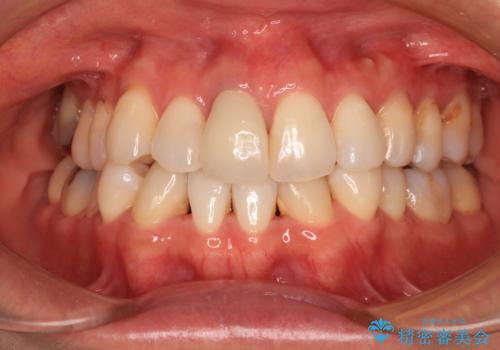

失活により変色した前歯 オールセラミッククラウンによる審美歯科治療

オールセラミッククラウンにて補綴治療を行うこととしました。

周りの歯と調和した、自然な仕上がりとなりました。